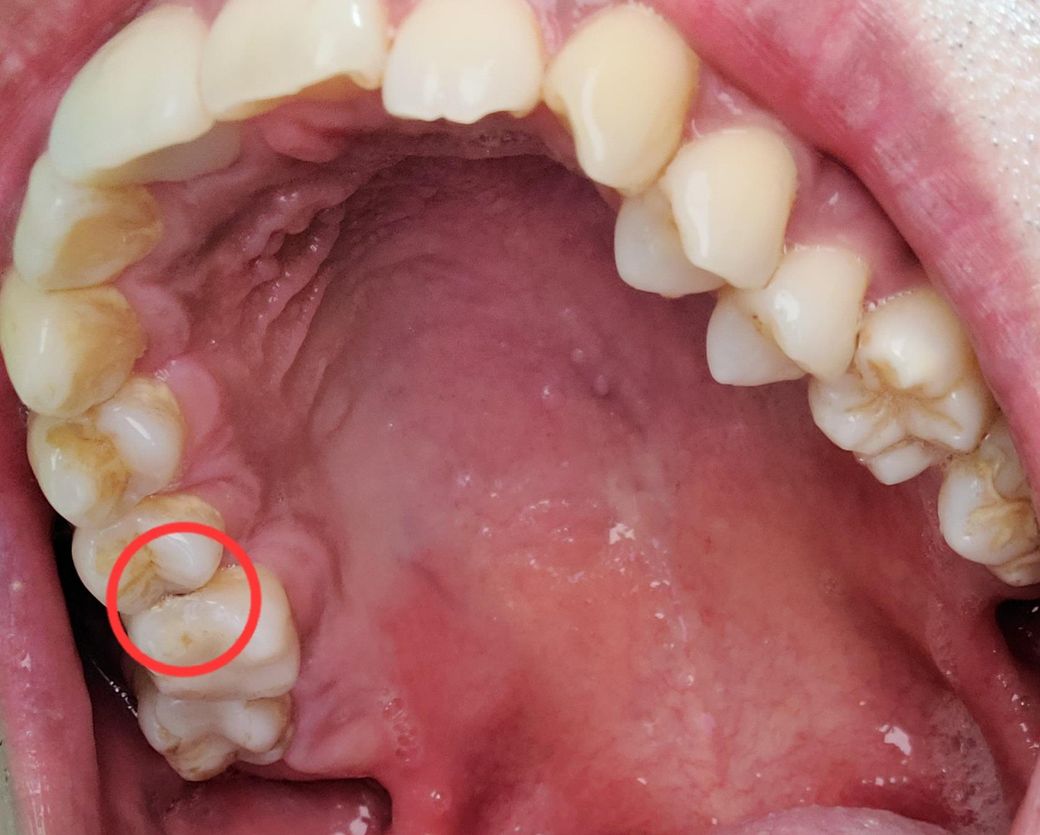

이가 가끔가다 가만히있을때 시큰거리는 것 같은데 한번봐주세요.

치과를 2군데 갔는데 한곳은 동그라미친곳이 인접면 충치라 인레이치아는 크라운으로 충치면은 인레이씌우자고 하고요.

다른곳은 체크표시친 치아가 문제일것 같긴 한데 씹을때 아파지거나 아니면 욱신거리는 통증이 생기면 신경치료해야한다고 말씀을 해주시더라고요.

도와주십쇼. 저는 동그라미 치아 앞 치아 부분이 시큰거리는 것 같은데 정확히는 모르겠습니다.

엑스레이상 명확히 보이는 깊은 충치는 없으나 육안 사진에선 충치가 보이긴 하네요 인레이까지는 가야할것 같고요 신경치료는 증상이 명확한게 아니면 아직 가능성이 높진 않네요